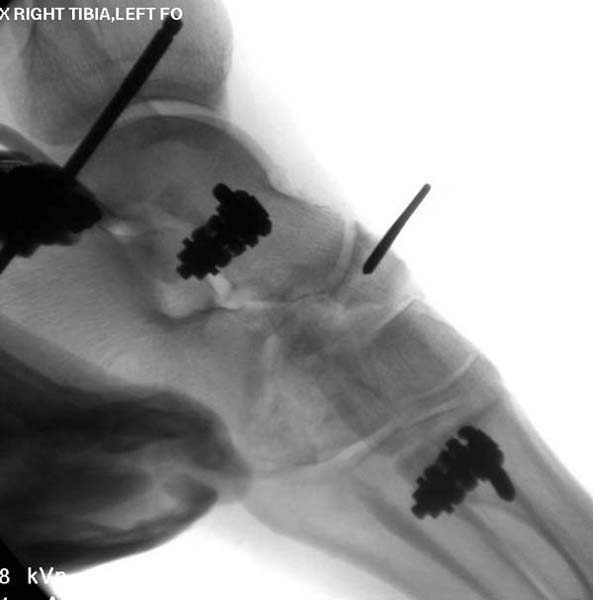

Через три дня повторная I&D, где через рану манипулировали дистальным фрагментом с установкой пары межфрагментарных шурупов. На рану вакуум и следующая обработка закончилась закрытием раны. Отек держался немного дольше, чем обычно.

После спадения отека вариантов фиксации много, включая мининвазивную технику, но данный случай закончили установкой простого аппарата Илизарова.